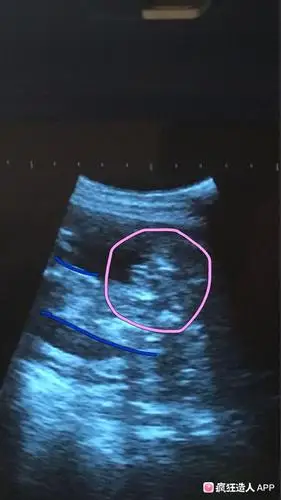

宝妈,看看我这个是男孩女孩啊!感觉是两个亮点,又像是三条线

求问我这三条线是肯定女宝了吗?

孕12周nt检查显示有三个亮点是男孩还是女孩

而三条线则是明显的女宝,如果没有看到明 显的三条线,就看两腿之间有

怀男孩b超有这些标志